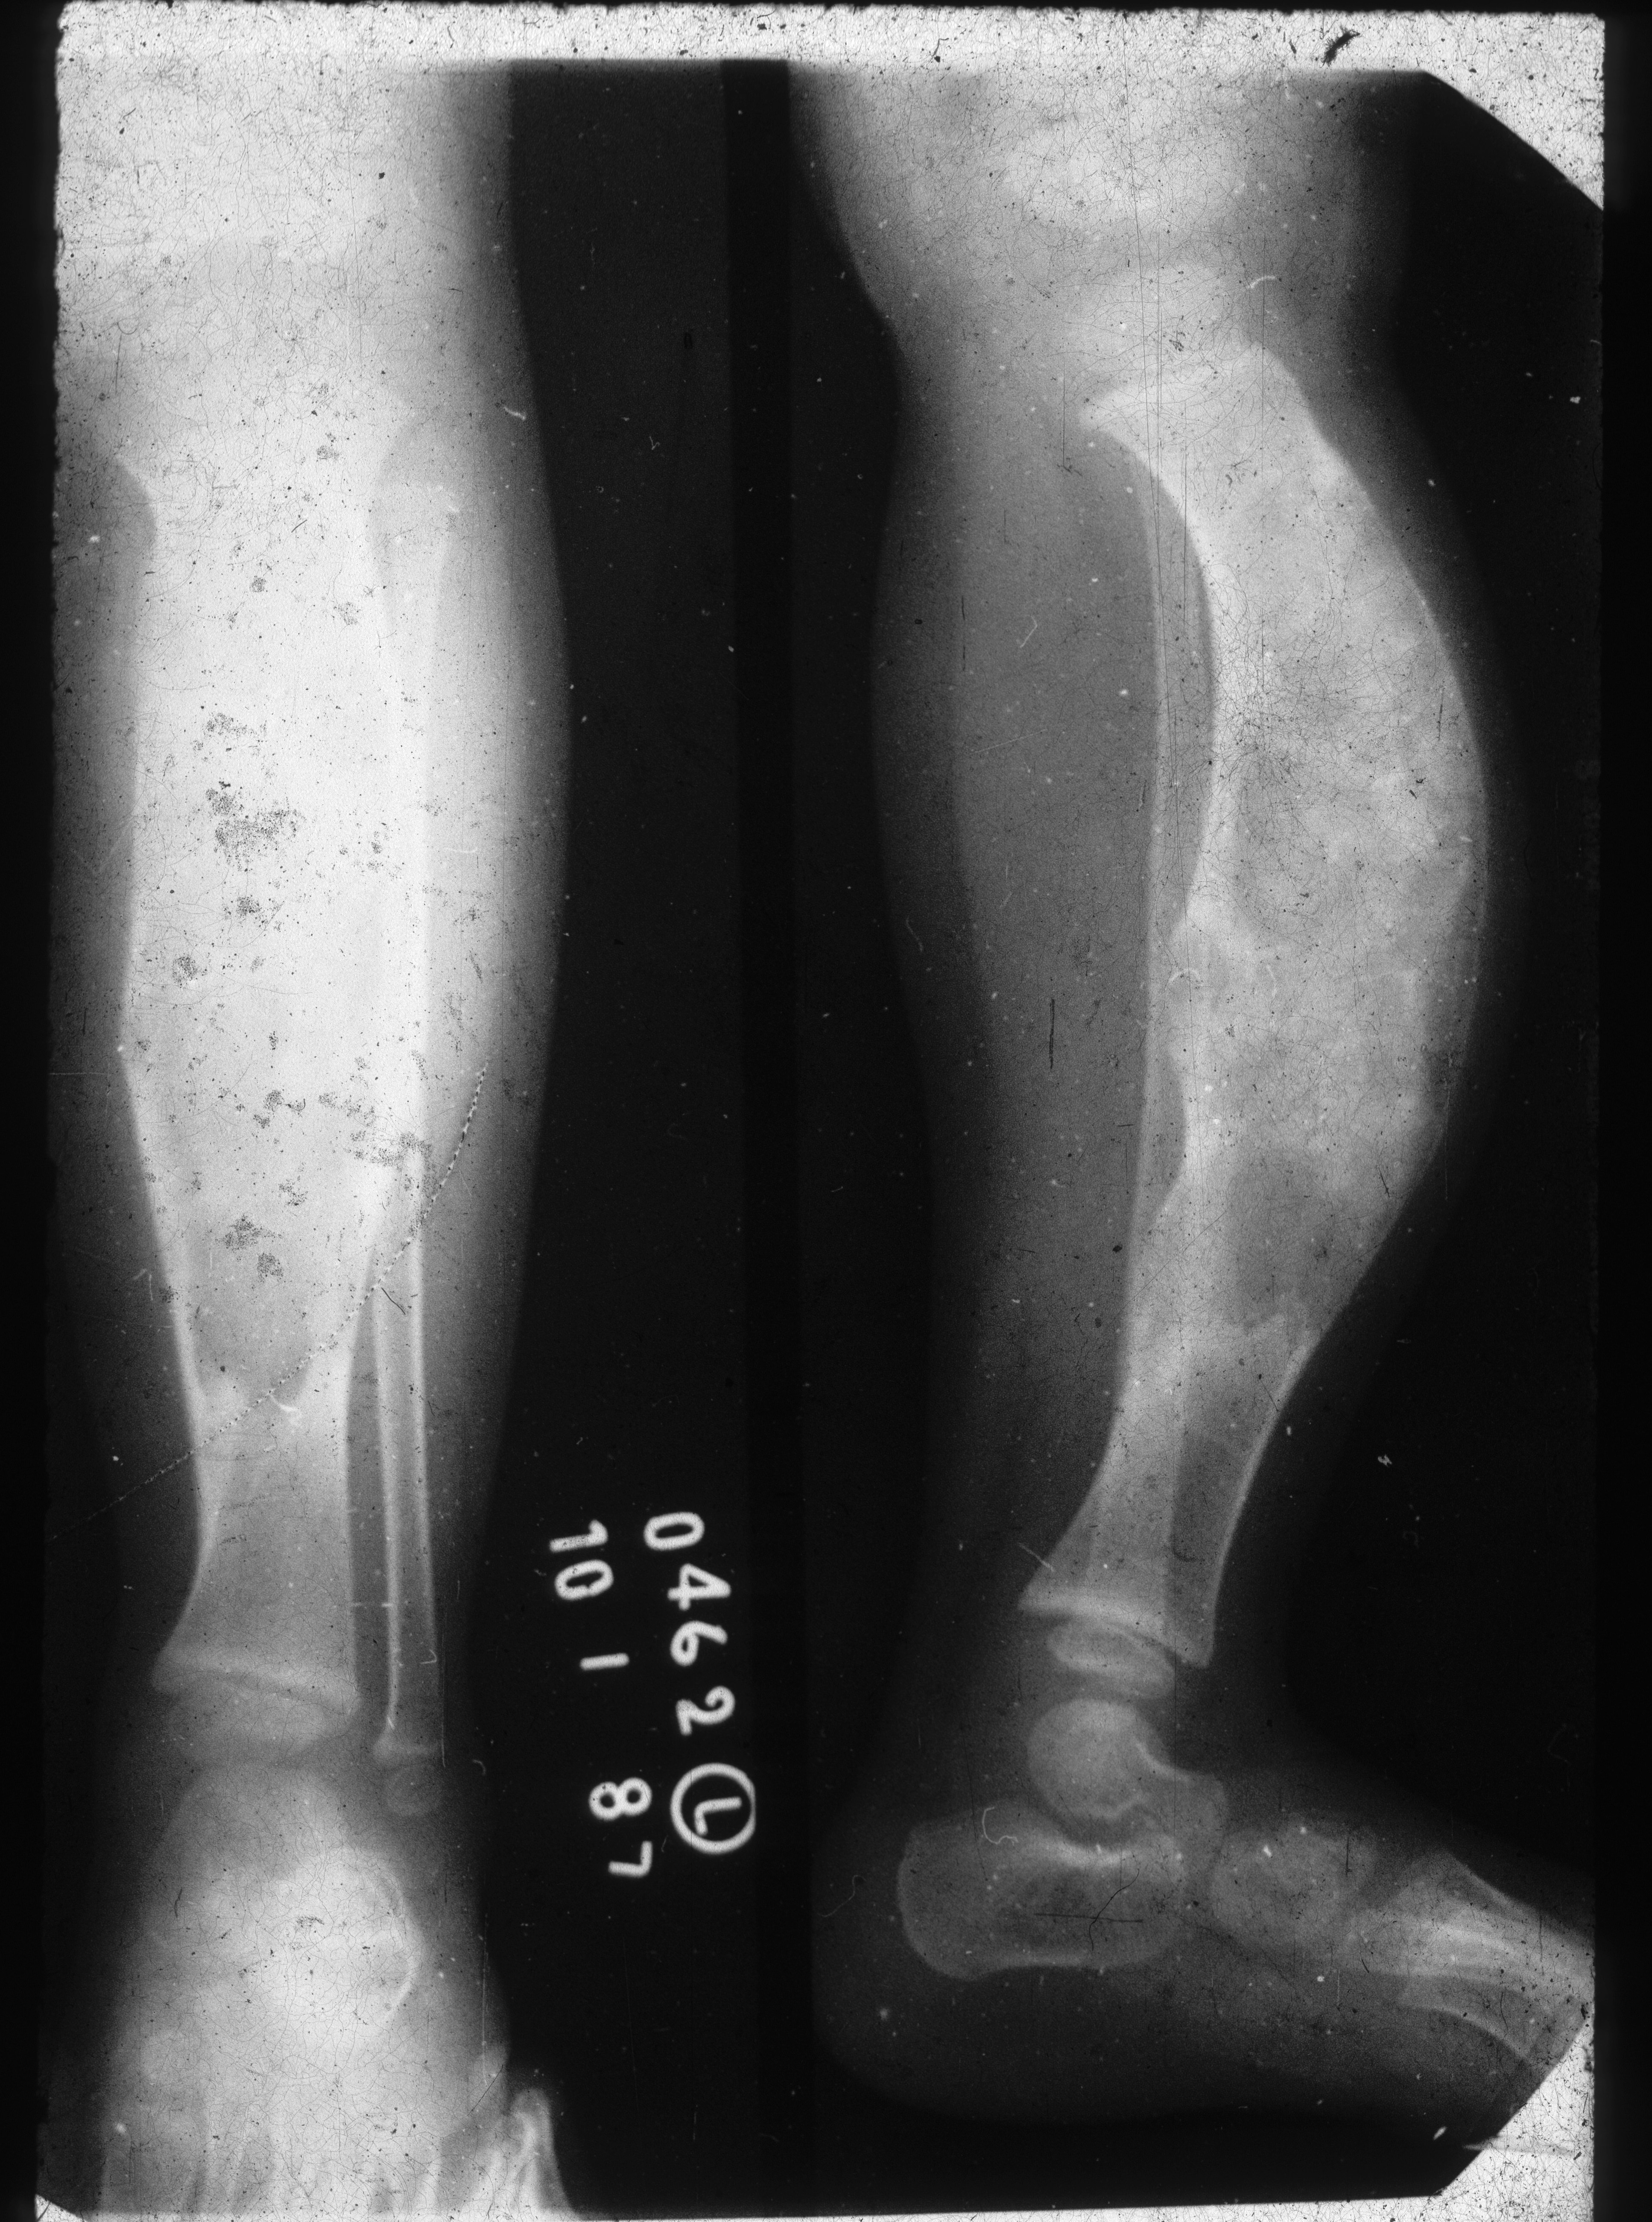

Fibro osseous dysplasia (ossifying fibroma) (Figure 29)

- Almost exclusively in tibia with anterior bowing

- Lesion begins in cortex

- Usually seen in children <10 years

Figure 29: Ossifying fibroma – Note the extensive changes in the tibia simulating FD. Anterior bowing is characteristic.